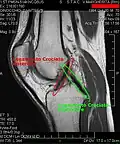

MRI

Both anterior cruciate ligament (ACL) and posterior cruciate ligaments (PCL) are hypointense on both T1 and T2 weighted images of MRI. However, some high signal striations are often seen at the distal part of the ACL, making ACL higher intensity than PCL on MRI scans.[20]